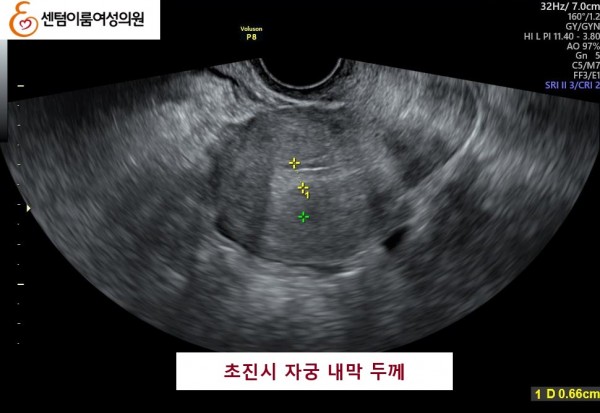

2024.12월 본원 내원시 오른쪽 난소에 자궁 내막증이 있었고, 자궁 내막 또한 얇았습니다.